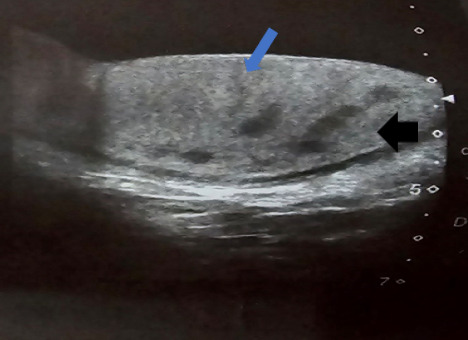

Extrapulmonary tuberculosis constitutes about 20% of all cases of tuberculosis. It involves organs other than the lungs, such as lymph nodes, the genitourinary tract, abdomen, skin, joints and bones, and meninges. Tuberculosis of the testis is a rare disease. The diagnosis of testicular tuberculosis could be confused with testicular cancer, sarcoidosis or metastases. Herein, we describe the ultrasonography of five patients with testicular tuberculosis. This case series highlights the importance of ultrasonography in the diagnosis of rare form of extra pulmonary tuberculosis.